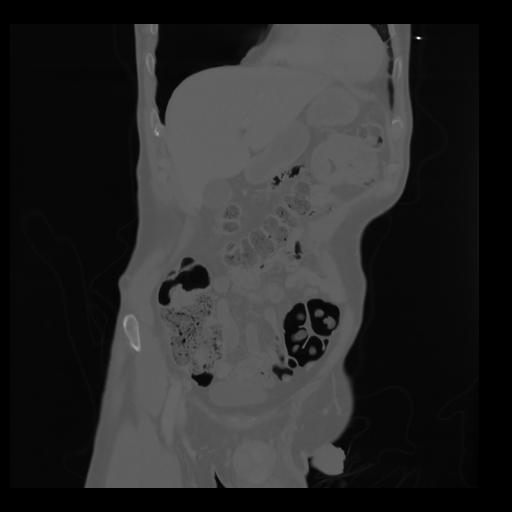

35 CUERPO,CE,Coronal,3.000,CUERPO,Coronal,